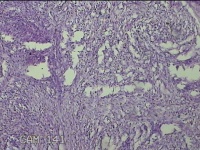

左大腿皮下结节

性别

女

年龄

30岁

临床诊断

皮下结节

一般病史

发现左大腿皮下结节1年余。

标本名称

大体所见

灰白粉红色组织1.7x0.8x0.3cm一个,表面带梭形皮肤 1.3x0.7cm,皮下见结节1.7x0.7cm一个,切开结节呈实性,切面灰白灰白粉红色,质中。

图1

良性病变。